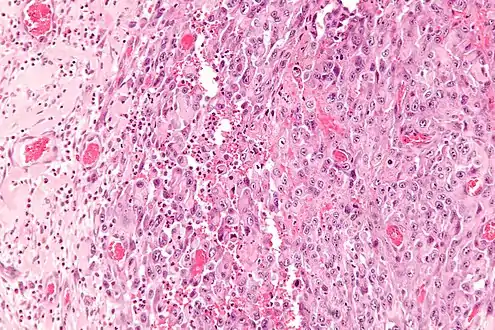

| Micrograph of an epithelioid sarcoma. H&E stain. | |

Histologically, epithelioid sarcoma forms nodules with central necrosis surrounded by bland, polygonal cells with eosinophilic cytoplasm and peripheral spindling.[3] Epithelioid sarcomas typically express vimentin, cytokeratins, epithelial membrane antigen, and CD34, whereas they are usually negative for S100, desmin, and FLI1 (FLI-1).[3] They typically stain positive for CA125.[4]